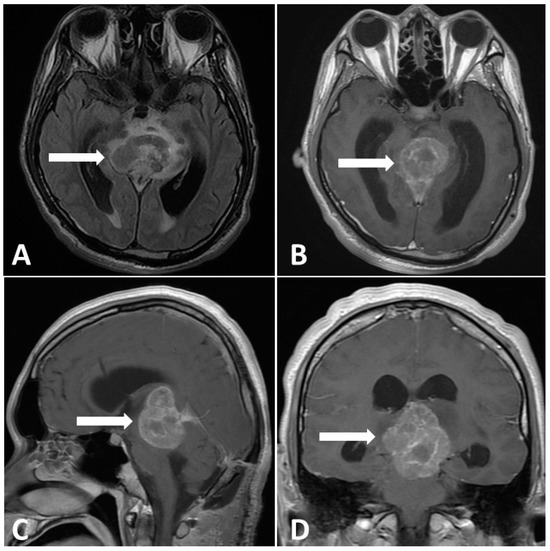

In the first postoperative week, the patient was capable of following instructions, even with the endotracheal tube and EVD in place, as a precaution against postoperative cerebral edema. During this period, the Karnofsky performance score (KPS) was 60. However, 2 weeks after surgical intervention, the Glasgow coma scale deteriorated to 7 from the normal level. Moreover, the KPS dropped to 20, accompanied by Parinoud’s syndrome. Thus, an emergency endotracheal tube was inserted due to impaired consciousness. A repeated MRI of the brain showed an enlarging heterogeneous enhancing mass, measuring 4.4 × 3.0 × 4.0-cm, occupying the pineal region and tectal plate and displacing the vein of Galen and inferior sagittal sinus with perifocal edema in bilateral thalamus and right basal ganglion as shown in Figure 4, compared with preoperative imaging. After explaining the outcome and risk of the subsequent therapeutic strategy to his family, chemotherapy with etoposide (600 mg) and cisplatin (140 mg) followed by ifosfamide (8000 mg) was administered in divided doses for 4 days with simultaneous intensive ventilation support. Unexpectedly, the patient recovered rapidly after chemotherapy. The tumor size dramatically decreased, as observed on MRI scan, with three cycles of chemotherapy. Moreover, radiotherapy with a total dose of 24 Gy in 22 fractions was administered over 3 weeks to the gross tumor before chemotherapy, followed by a local boost total dose of 16 Gy in 10 fractions over 2 weeks to the residual tumor after chemotherapy.

Figure 4.

Postoperative MRI performed 2 weeks after surgery. (A) Enlargement pineal tumor with perifocal edema on T2-FLAIR images. (B–D) Gadolinium-enhanced MRI, revealing a large pineal region tumor with heterogenous contrast enhancement.